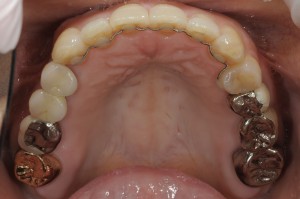

欠損補綴治療には、ブリッジ、入れ歯(義歯)、インプラント、と大きく分けて3つの方法があります(詳細はコチラ)が、今回ご紹介するのは「インプラント」のケースです。また、インプラント治療と歯列矯正治療を併用したケースでもあります。

まず、破折した歯の抜歯を行う前に、奥の部分にインプラントを埋入し、仮の歯を入れておきます。インプラントを支えにすることで歯列矯正の期間短縮が可能になり、確実な矯正治療を行う事ができます。(矯正治療はパートナーのよしかわ矯正歯科で行いました。)

前歯の矯正治療が終了した段階で、折れた歯の部分に、もう一つインプラントを埋入しました。

その後、インプラントの固定期間(約3か月)を待ち、上部構造物(歯の頭の部分)を製作して治療は完了となります。

インプラントによる欠損補綴と矯正治療を併用したため、治療期間は長くなってしまいましたが、噛み合わせを整えることで、今後はしっかりとした食事が摂取できるようになると考えております。